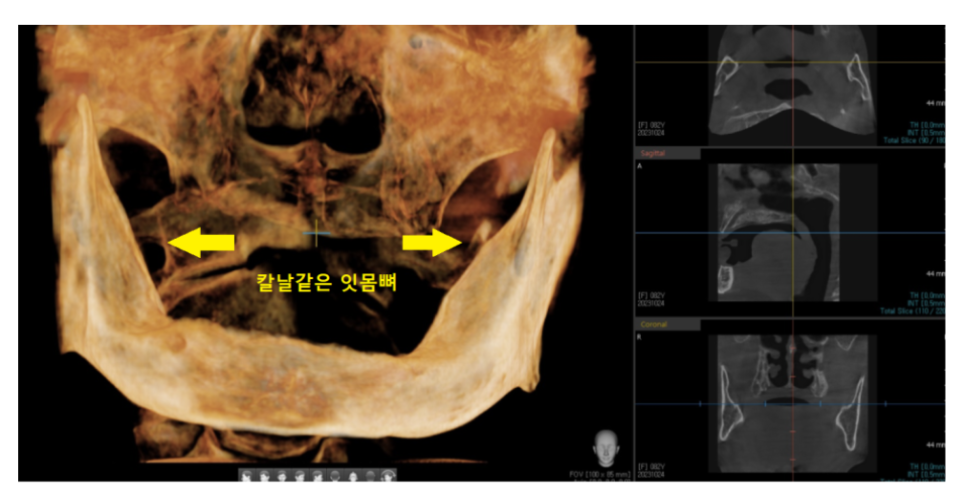

턱뼈가 많이 흡수되어 일반 임플란트가 어려운 경우

특히 틀니를 오래 쓰신 환자분.

어금니 뼈가 부족하여 임플란트 수술이 어려운 환자분들이

분석이 중요하기 때문에

CT 촬영도 선행되어야하고요.